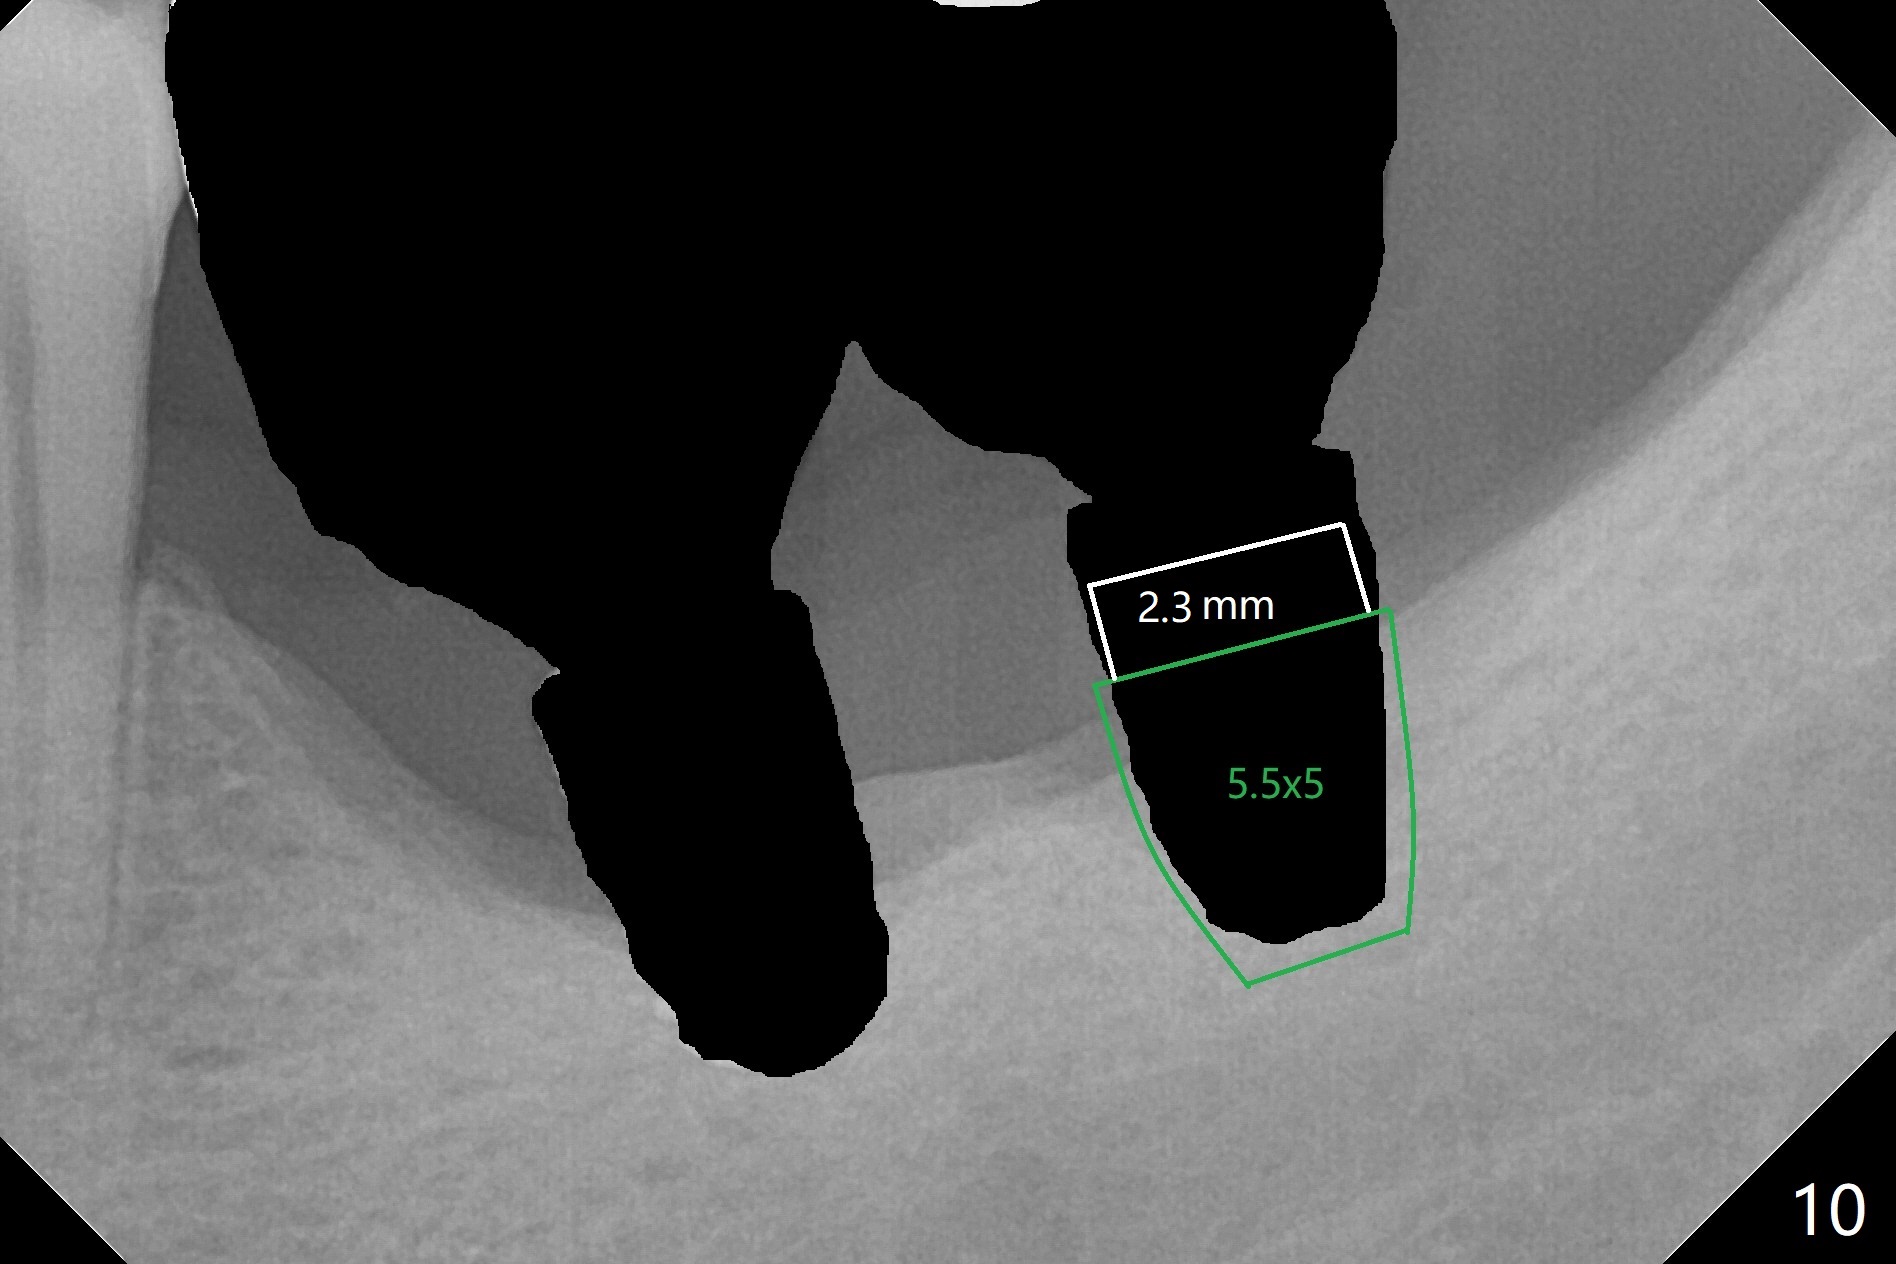

Preop photo shows severe mesial tilt of the tooth #18 (Fig.1). After extraction, the osteotomy is established in the apical end of the socket, where the buccolingual width is limited. It appears that an extra wide implant (5.9 mm) may perforate one of buccolingual plates. On the other hand, the buccal plate (Fig.2 double arrows) is intact and approximately 2 mm tall, whereas the lingual one is thin and lower. Initial osteotomy confirms that bone heights at #18 and 19 are 6 and 8 mm, respectively. Counting 2 mm of the buccal plate and bone graft lingually, a 8 mm long implant may be a practical option at the site of #18. After initial placement of two of 5x8 mm SM implants (Fig.3), the depth of the implant at #19 is adjusted twice (Fig.4,5). With placement of autogenous and allograft (Vanilla, Fig.5 *)) and abutments, a piece of cotton pellet is placed in each abutment well (access, Fig.6 *). Periodontal dressing is applied to the abutment wells for additional retention (Fig.7 *). Due to local poor oral hygiene, splinted provisional is fabricated 4 months postop (Fig.8) in preparation for limited orthodontic uprighting the tooth #20. The patient has pain with mastication at #18 eleven months post cementation (Fig.9). It appears that both of the implants should be removed with immediate replacement and bone graft. Prepare 4 PRF and sticky bone. The new implant will be 5.0 or 5.5x5 mm (Fig.10 green) with 2.3 mm platform (white). A block graft will be harvested from the ipsilateral ramus using 9/8 and 6/5 mm trephine burs for 2-3 mm in depth (Fig.11 blue). The ring graft will be seated around the platform over the implant (Fig.12).